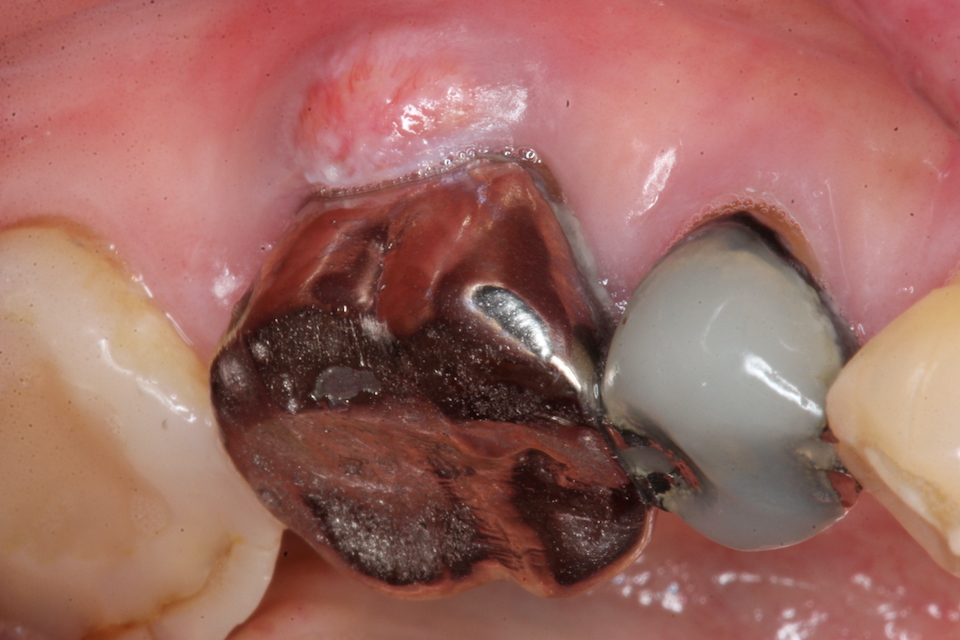

今日の抜歯再植術シリーズ34.1

60代女性、左下6、歯根破折、GA前回のつづきなんですが、2年程前に同じ症状が出た時の画像を探したのでご供覧。https://plaza.rakuten.co.jp/mabo400dc/diary/202505170000/すでに何年も前からクラックが入っていたり、神経は取ってあるものの根管が緊密に根管充填されていなかったり、根尖口が閉鎖していなかったり、そもそも冠やメタルコアのセメント合着が効いていなくて隙間だらけで硫酸塩還元細菌の住処となっていたりとどうしようもない状況になっていたわけです。こういうことは通常の歯科治療では普通のことだと思っても良いと思います。要するに歯科治療は上手くいくことの方が稀なので、してはいけない!どんな方法を採っても、技術的に優れた術者が行ってもです。特に神経を取る治療は歯の寿命が30年位になるというのが本当のところです。まあ、30年も持つのなら患者も何時何処の歯医者でやったかも忘れているだけのお話というお寒い現状が実態です。人生50年、60まで生きれば御の字の時代ならよかったのですが、今はそうではない。このサイトではどうすれば神経を取らずに歯の寿命を伸ばすことができるか?という誰でもできる方法を無料公開していますので全部ご覧ください。記事がたくさんあるので大変でしょうが、まぁ、少なくとも高校卒業程度の物理化学生物の基礎知識は必要です。では時系列でどうぞ腫れている冠を除去冠もコアも歯根内部も真っ黒。硫酸塩還元細菌の代謝産物(うんこ)のFeS(硫化鉄)にまみれている。細菌が繁殖できる隙間があったということで、セメント(接着剤)合着系の修復物には多かれ少なかれ普通にあることです。クラックがありすでに割れているということが分かる。つづく